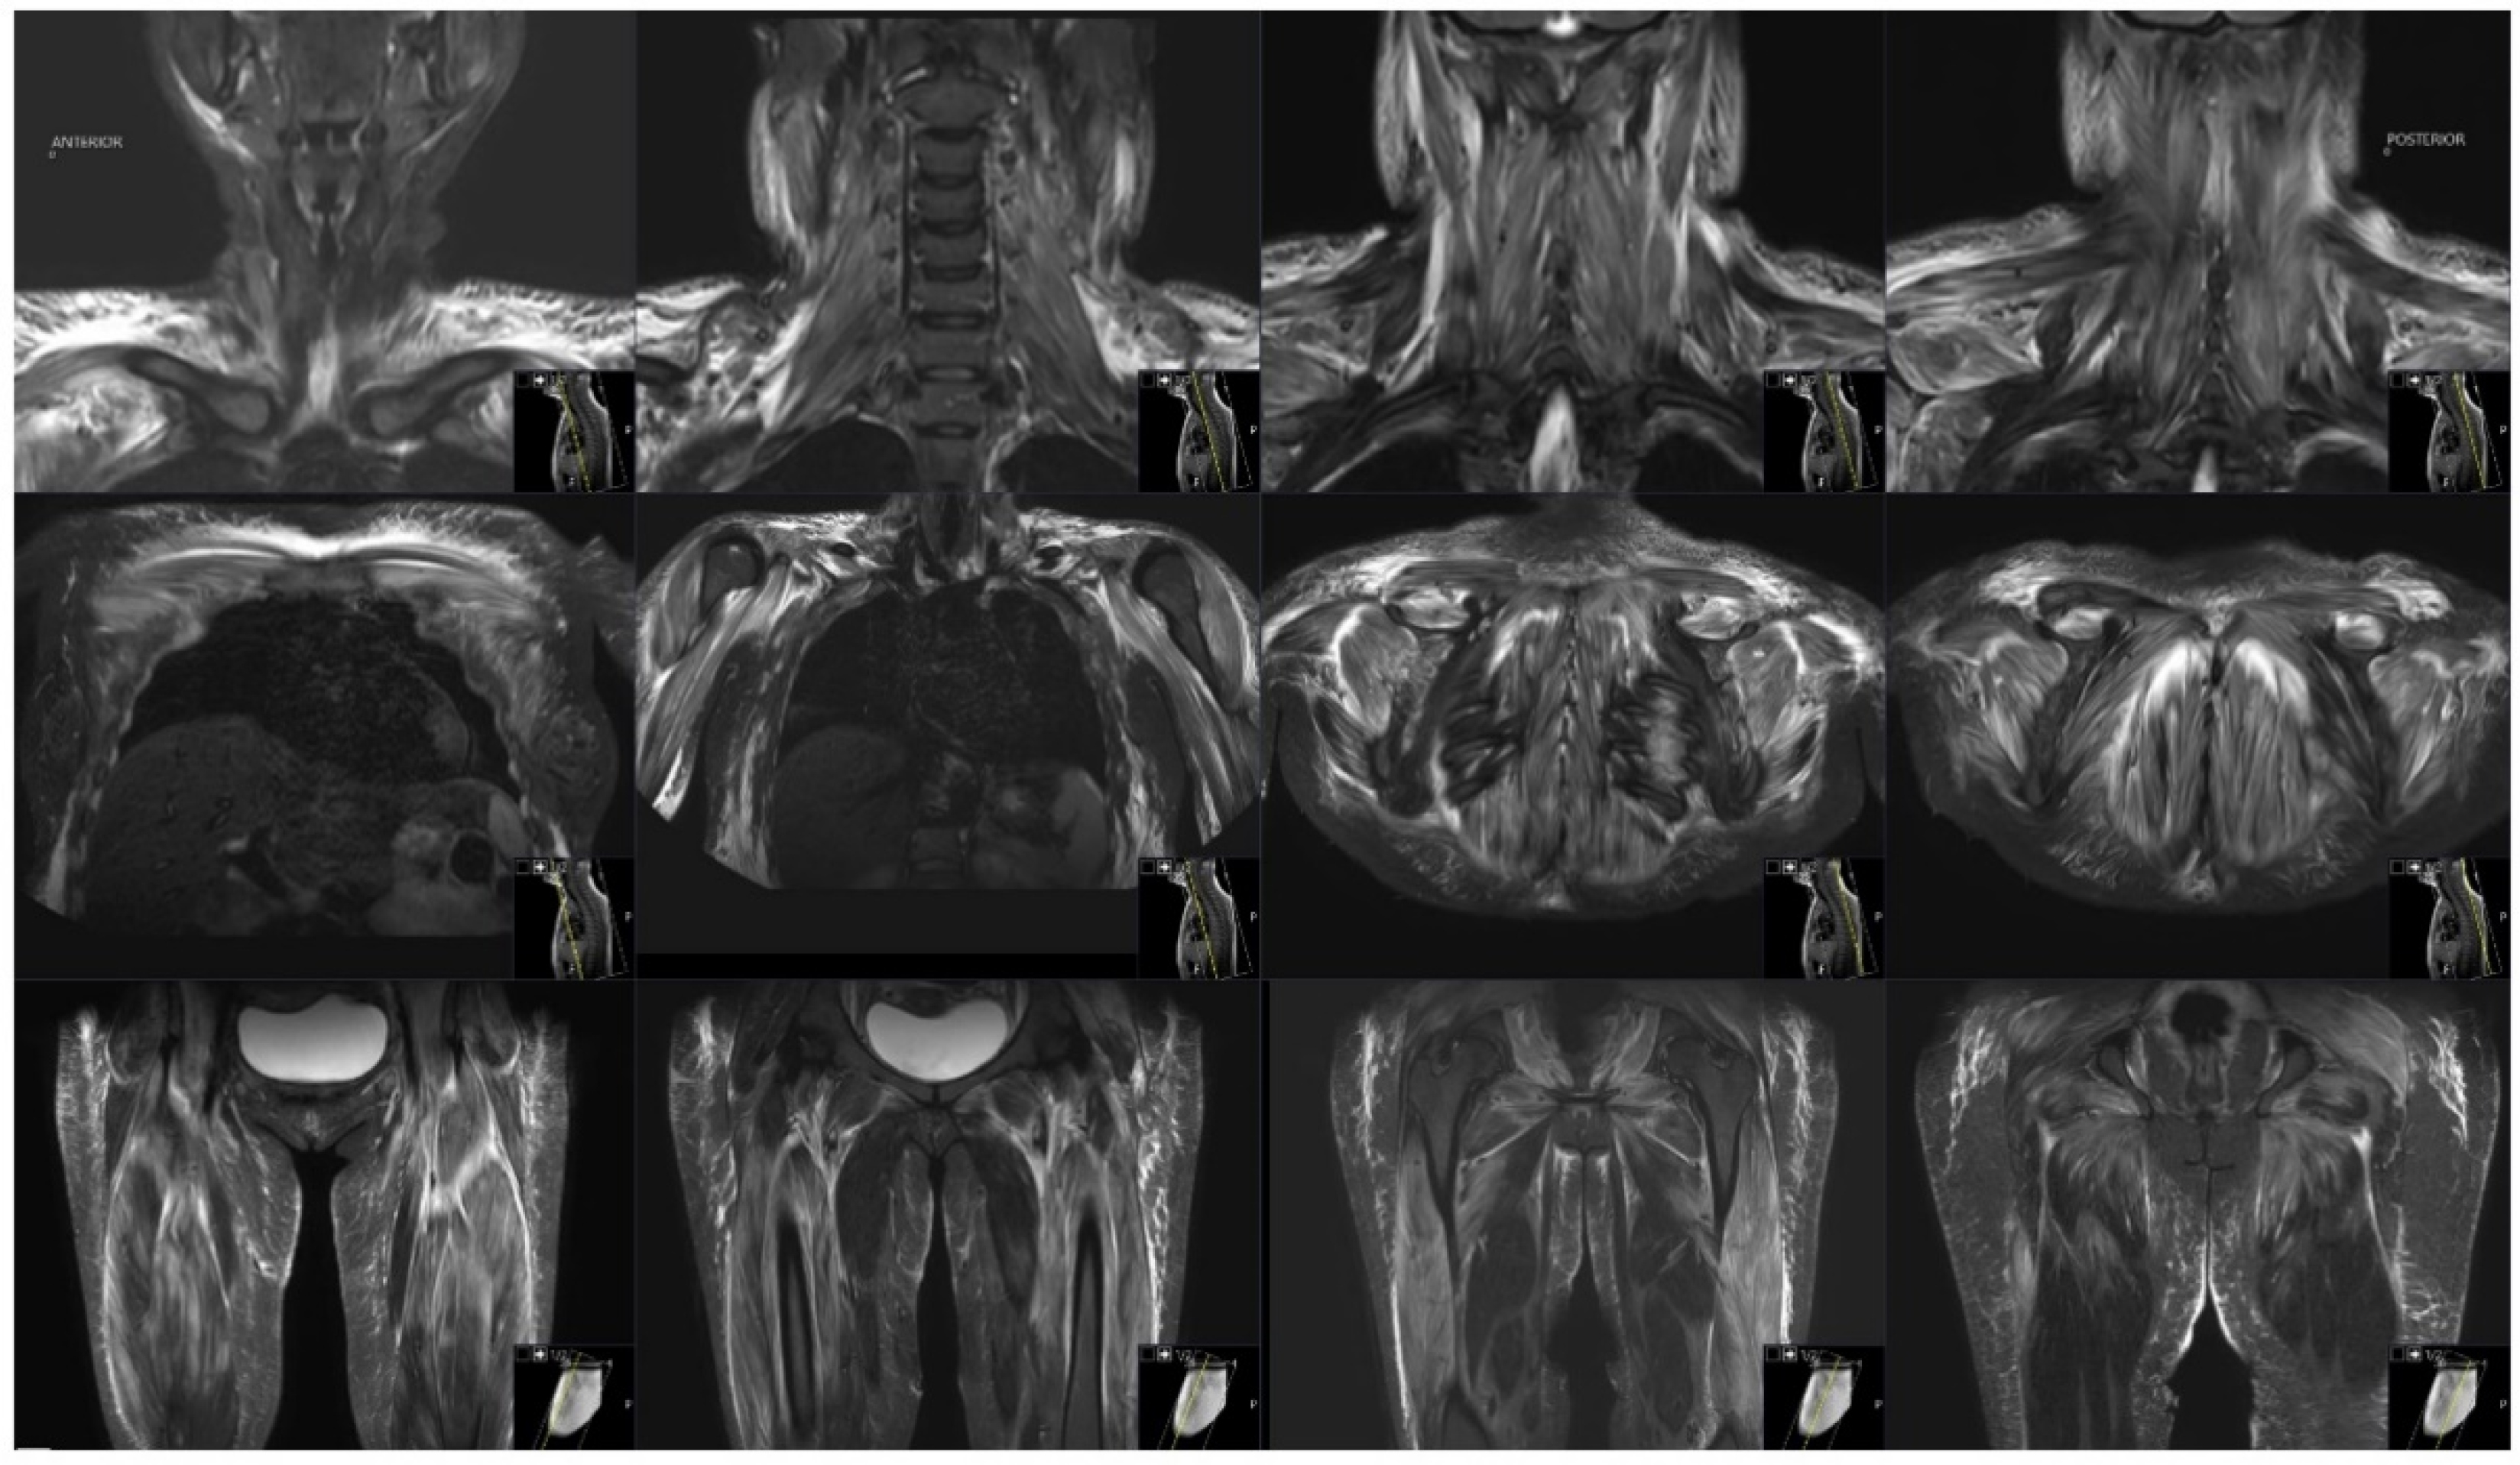

3.1. Case Representation